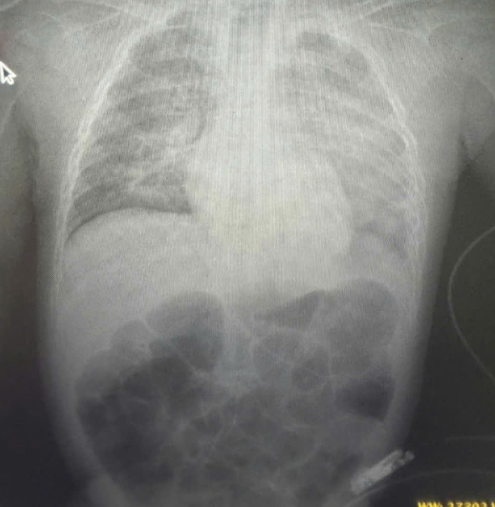

Cấp cứu thành công trẻ 8 tháng tuổi bị sởi biến chứng nghiêm trọng

Thứ Hai, ngày 12/05/2025 01:42Mới đây, Bệnh viện Sản Nhi Vĩnh Phúc đã cứu sống trẻ bị sởi biến chứng rất nặng gây viêm phổi, suy hô hấp, ARDS, sốc nhiễm khuẩn... Khoa Hồi sức tích cực chống độc, Bệnh viện...